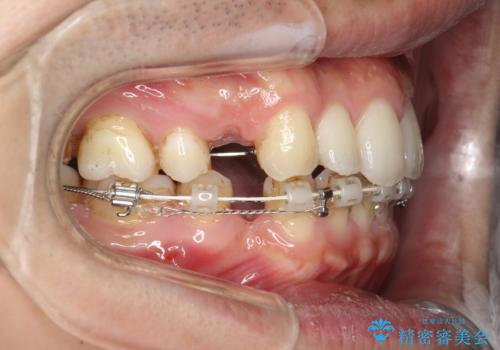

前歯の隙間を閉じたい 口元も下げたい ハーフリンガルによる抜歯矯正

上下左右の歯を1本ずつ抜歯しして、上顎の前歯を後方に移動させるのと、正中の隙間を閉じる計画としました。

装置はなるべく目立たないものをご希望でしたので、ハーフリンガルを選択されました。

抜歯をせず上顎の正中離開のみの矯正もできましたが、患者様と相談して口元の改善も同時に行うために抜歯矯正の計画としました。